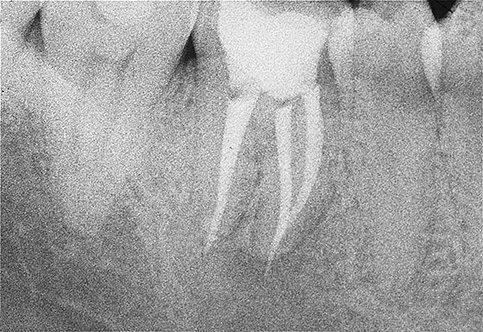

I batteri all’interno dei canali proliferandosi, possono dunque dar luogo ad un processo infiammatorio all’apice della radice che si può manifestare nei quadri clinici enunciati e apparire radiograficamente come una zona di radiotrasperenza dell’osso periapicale.

Dopo aver risolto l’evento infiammatorio acuto, nella maggior parte dei casi per mezzo di una terapia antibiotica sistemica, questi denti devono essere curati al fine di rimuovere le cause che sostengono l’infezione cronica. La terapia prevede un ritrattamento endodontico, ovvero un completo rifacimento della devitalizzazione, con l’obiettivo di eliminare la carica batterica presente nei canali radicolari.

E’ molto importante monitorare nel tempo il ritrattamento, eseguendo radiografie di controllo a distanza che documenteranno le modificazioni morfologiche della lesione periapicale e consentiranno al clinico di pronunciarsi in merito alla guarigione e alla prognosi del singolo caso.